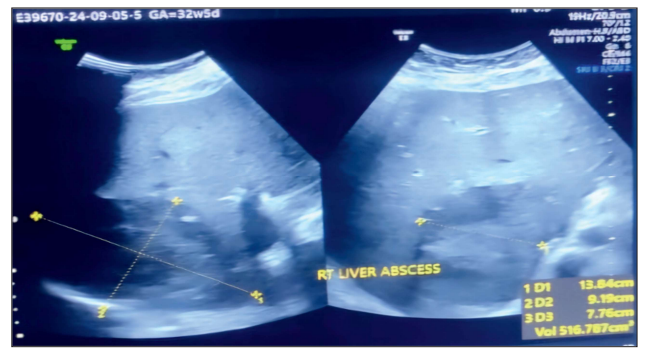

Introduction: Amoebic liver abscesses, primarily due to Entamoeba histolytica, are prevalent in tropical regions. Undetected, they can reach huge sizes causing febrile illness with features of acute abdomen. Early diagnosis and timely intervention are more crucial in pregnancy to prevent complications not only to mother (like rupture, sepsis and septic shock), but also to fetus. This case discusses the diagnostic and management problems in one such gravid woman with a gigantic Liver abscess presenting with sepsis. Case Presentation: We present a case of a 39 years, Primigravida at 33 weeks of gestation who presented to emergency with high grade fever, severe pain abdomen, abdominal distension, nausea-vomitting and constipation. She had a qSOFA score of 10 and was admitted in the ICU with Sepsis and Acute abdomen. Investigations revealed a Liver abscess of 1000cc in the left lobe. ICU management was done followed by percutaneous drainage of the abscess was done and patient was started on parenteral meropenem and metronidazole along with close feto-maternal monitoring. Serological tests confirmed Entamoeba histolytica. She was discharged with a healthy fetus after 9 days and sent home on Tab metronidazole. Discussion: This case highlights the importance of considering amoebic liver abscess in patients from endemic areas presenting with fever and right upper quadrant pain. Diagnostic imaging, combined with serology, plays a pivotal role in prompt diagnosis. Antiparasitic therapy remains the cornerstone of treatment, drainage can be considered to hasten the response specially in cases with large collection while other surgical interventions are kept for complicated cases. Acute